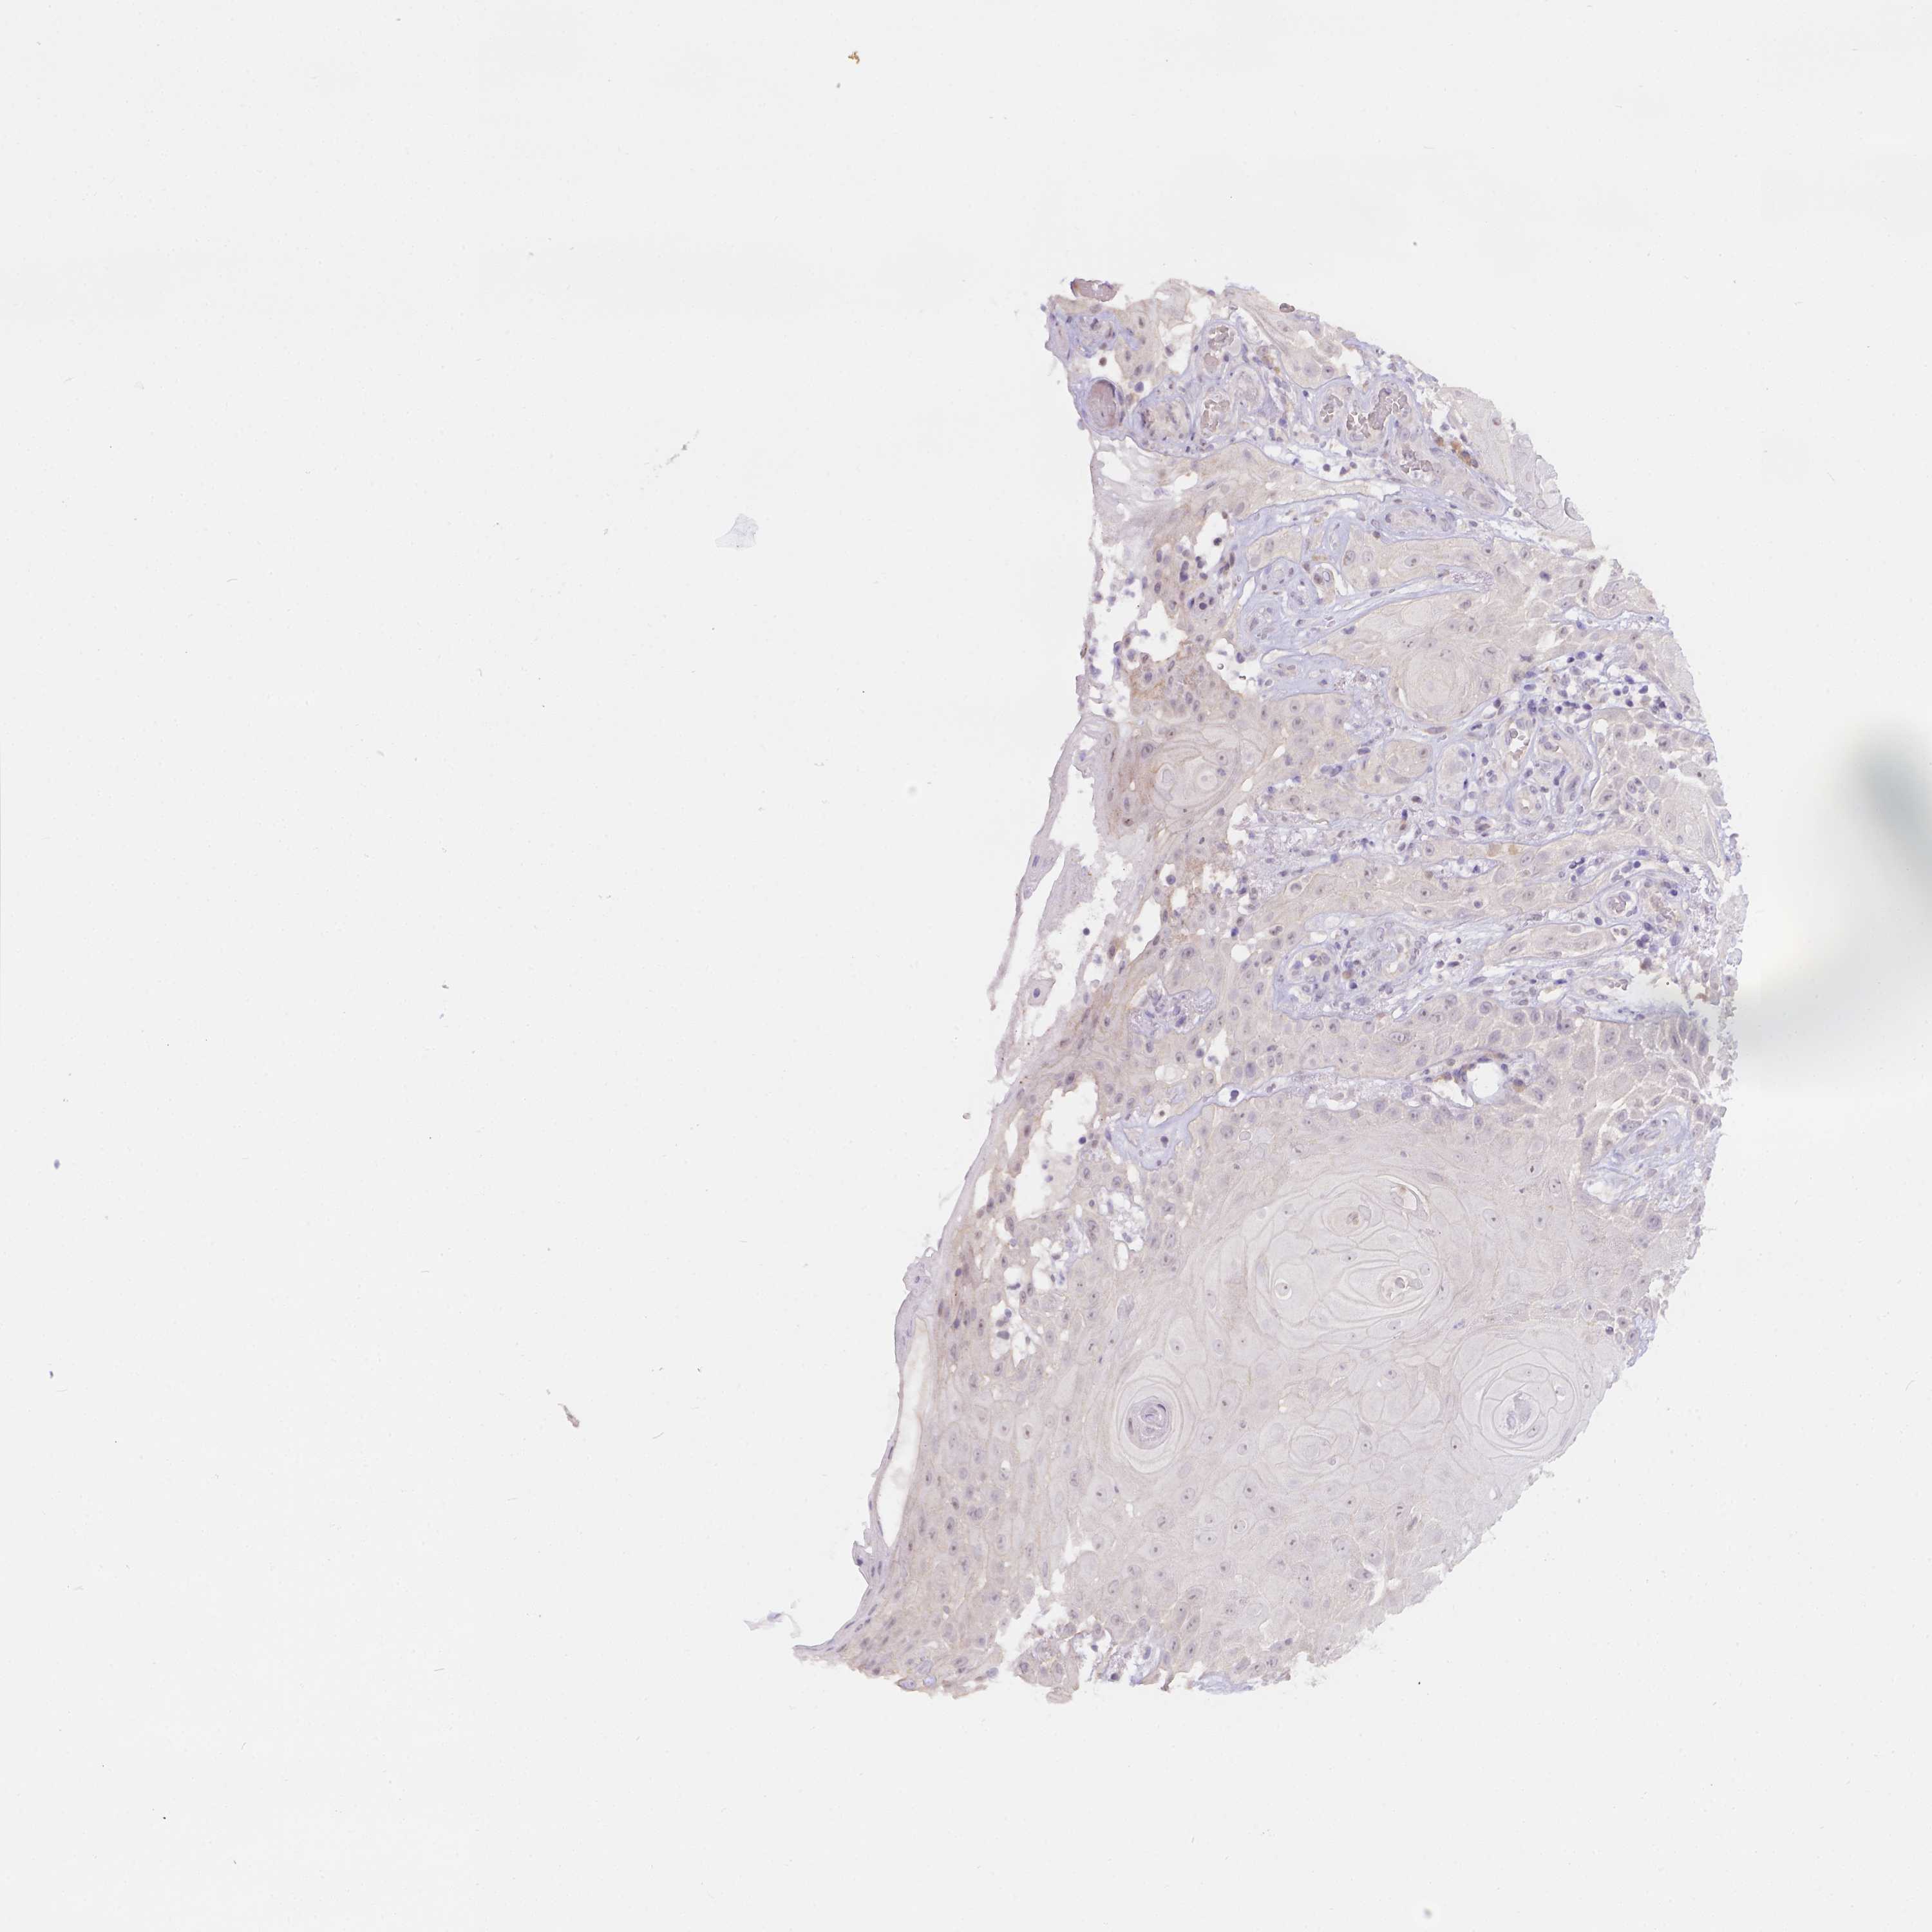

Basal cell and squamous cell cancer

SKIN CANCER - Protein expressioni

A mouse-over function shows sample information and annotation data. Click on an image to view it in a full screen mode. Samples can be filtered based on level of antibody staining by selecting one or several of the following categories: high, medium, low and not detected. The assay and annotation is described here.

Each image is clickable and will lead to virtual microscopy that enables deeper exploration of all samples and also displays staining intensity scores, fraction scores and subcellular localization as well as patient and tissue information for each sample.

Antibody HPA066754

Basal cell carcinoma

Squamous cell carcinoma, NOS